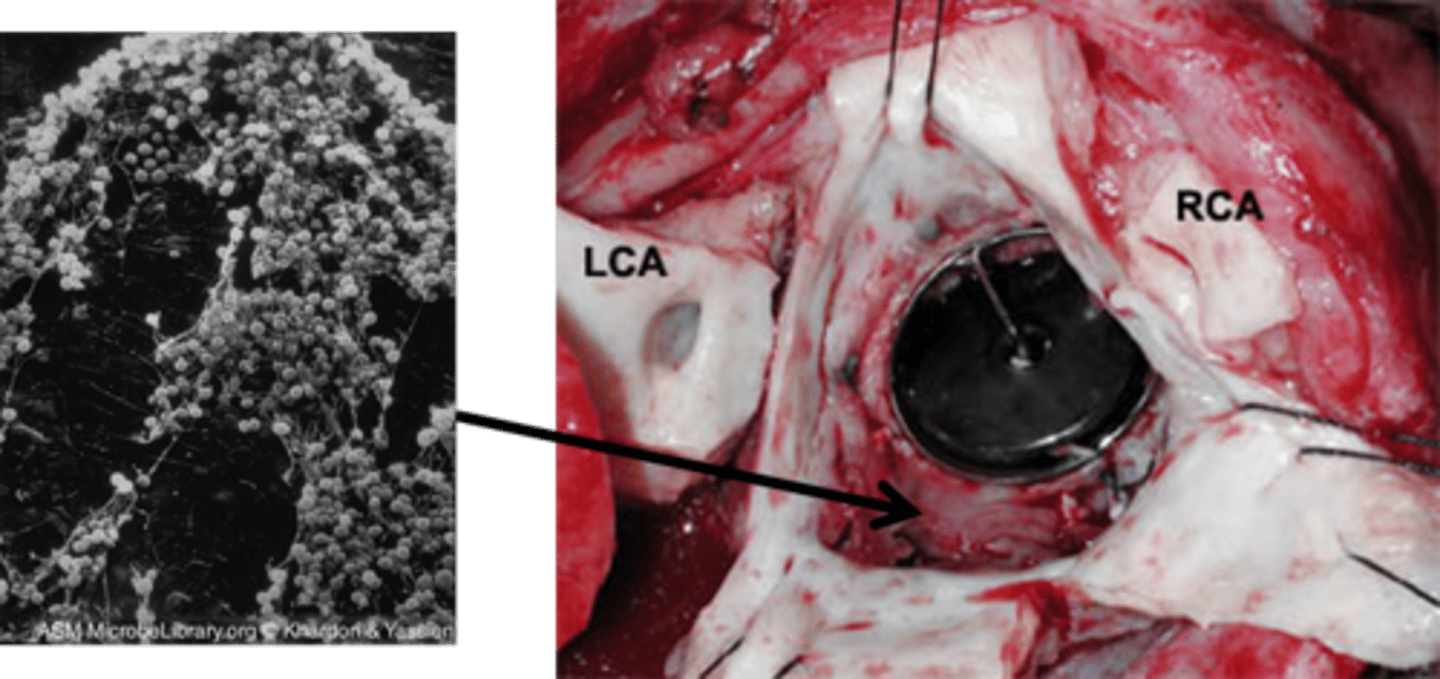

Mycoses.

Candida albicans.

Fungi, Thrush, diaper rash, "yeast" infections, systemic infections.

Candida auris.